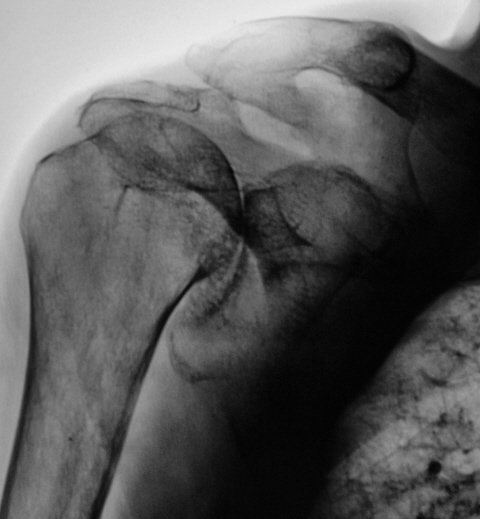

Валентин Львович! Думаю, что имела место травма в виде перелома ключицы и разрыва ключично-акромиального сочленения. Перелом ключицы консолидировался. А разрыв остался с образованием нового сустава (подвижного). Посттравматический артроз плечевого сустава.

Но ведь это можно считать как подвывих?